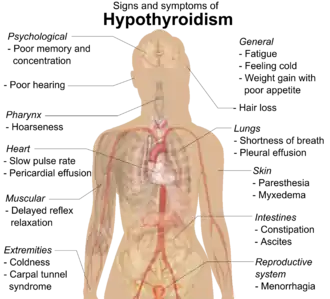

Early on, symptoms may not be noticed.[3] Over time, the thyroid may enlarge, forming a painless goiter.[3] Most people eventually develop hypothyroidism with accompanying weight gain, fatigue, constipation, hair loss, and general pains.[1] After many years, the thyroid typically shrinks in size.[1] Potential complications include thyroid lymphoma.[2] Further complications of hypothyroidism can include high cholesterol, heart disease, heart failure, high blood pressure, myxedema, and potential problems in pregnancy.[1]

As lymphocytic infiltration progresses, patients may exhibit signs of hypothyroidism in multiple bodily systems, including, but not limited to, a larger goiter, weight gain, cold intolerance, fatigue, myxedema, constipation, menstrual disturbances, pale or dry skin, and dry, brittle hair, depression, and ataxia.[14][10] Extended thyroid hormone deficiency may lead to muscle fibre changes, resulting in muscle weakness, muscle pain, stiffness, and rarely, pseudohypertrophy.[15] Patients with goiters who have had autoimmune thyroiditis for many years might see their goiter shrink in the later stages of the disease due to destruction of the thyroid.[1] Graves disease may occur before or after the development of autoimmune thyroiditis.[16]

While rare, more serious complications of the hypothyroidism resulting from autoimmune thyroiditis are pericardial effusion, pleural effusion, both of which require further medical attention, and myxedema coma, which is an endocrine emergency.[10]

Many symptoms are attributed to the development of Hashimoto's thyroiditis. Symptoms can include: fatigue, weight gain, pale or puffy face, feeling cold, joint and muscle pain, constipation, dry and thinning hair, heavy menstrual flow or irregular periods, depression, a slowed heart rate, problems getting pregnant, miscarriages,[17] and myopathy.[15] Some patients in the early stage of the disease may experience symptoms of hyperthyroidism due to the release of thyroid hormones from intermittent thyroid destruction[10][18] (also called "destructive thyrotoxicosis").[5] In non-medical settings, the term "flare" is used to refer to a sudden exacerbation of symptoms, whether hyper or hypo.[19]

While most symptoms are attributed to hypothyroidism, similar symptoms are observed in Hashimoto's patients with normal thyroid hormone levels.[20][21][13] According to one study, these symptoms may include lower quality of life, and issues of the "digestive system (abdominal distension, constipation and diarrhea), endocrine system (chilliness, gain weight and facial edema), neuropsychiatric system (forgetfulness, anxiety, depressed, fatigue, insomnia, irritability, and indifferent [sic]) and mucocutaneous system (dry skin, pruritus, and hair loss)."[22]